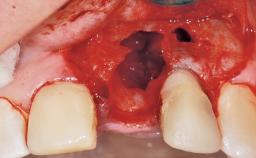

Late Flapless Placement of an Implant in a Maxillary Left Central Incisor Site

A 39-year-old male patient presented with a chief complaint of discomfort and gingival discoloration around his maxillary left central incisor. He was in good general health and was a non-smoker. His past dental history was significant because of the traumatic fracture of tooth 21 in a sporting accident at age 13. Initial dental treatment included endodontic therapy and a full-coverage restoration. The patient became symptomatic 5 years later, when structural failure of the tooth resulted in the dislodgment of the crown. Endodontic retreatment, apical surgery, and post-and-core restoration were performed.

Bone Augmentation Horizontal|Staged

Augmentation Materials Xenogenous|Membrane

Bone Volume Deficient horizontally, requiring prior grafting